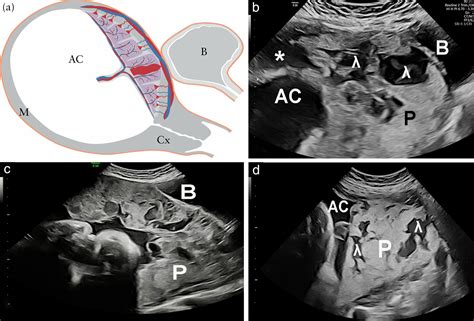

The placenta is a temporary organ that develops in the uterus during pregnancy. It serves as a lifeline between the mother and the fetus, facilitating the exchange of nutrients, gases, and waste products. Lakes In The Placenta refer to small, fluid-filled spaces within the placental tissue. These lakes are not typically visible to the naked eye but can be detected through advanced imaging techniques and histological examinations.

• Ultrasound Imaging: High-resolution ultrasound can sometimes detect the presence of lakes, although this method is not always reliable.

• Magnetic Resonance Imaging (MRI): MRI provides detailed images of the placenta and can help identify lakes more accurately.

• Histological Examination: Post-delivery, a histopathological examination of the placenta can confirm the presence of lakes.

While these methods are effective, they are not routinely used in all pregnancies. Lakes In The Placenta are often discovered incidentally during routine prenatal check-ups or post-delivery examinations.